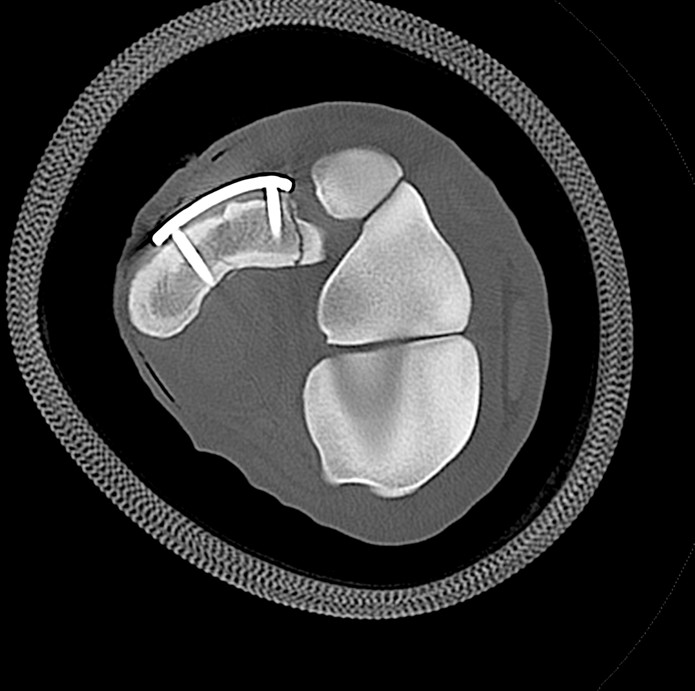

Distal Limb of the Standing Horse

Examinations up to the radius or the tibia

Standing, yet non weight bearing examinations allow CT arthrography without general anesthesia and reduce artifacts from load bearing

The 0.5mm slice size combined with the latest algorithms and over 80 reconstruction filters allow imaging of the smallest lesions in ligaments, tendons, and hyaline cartilage